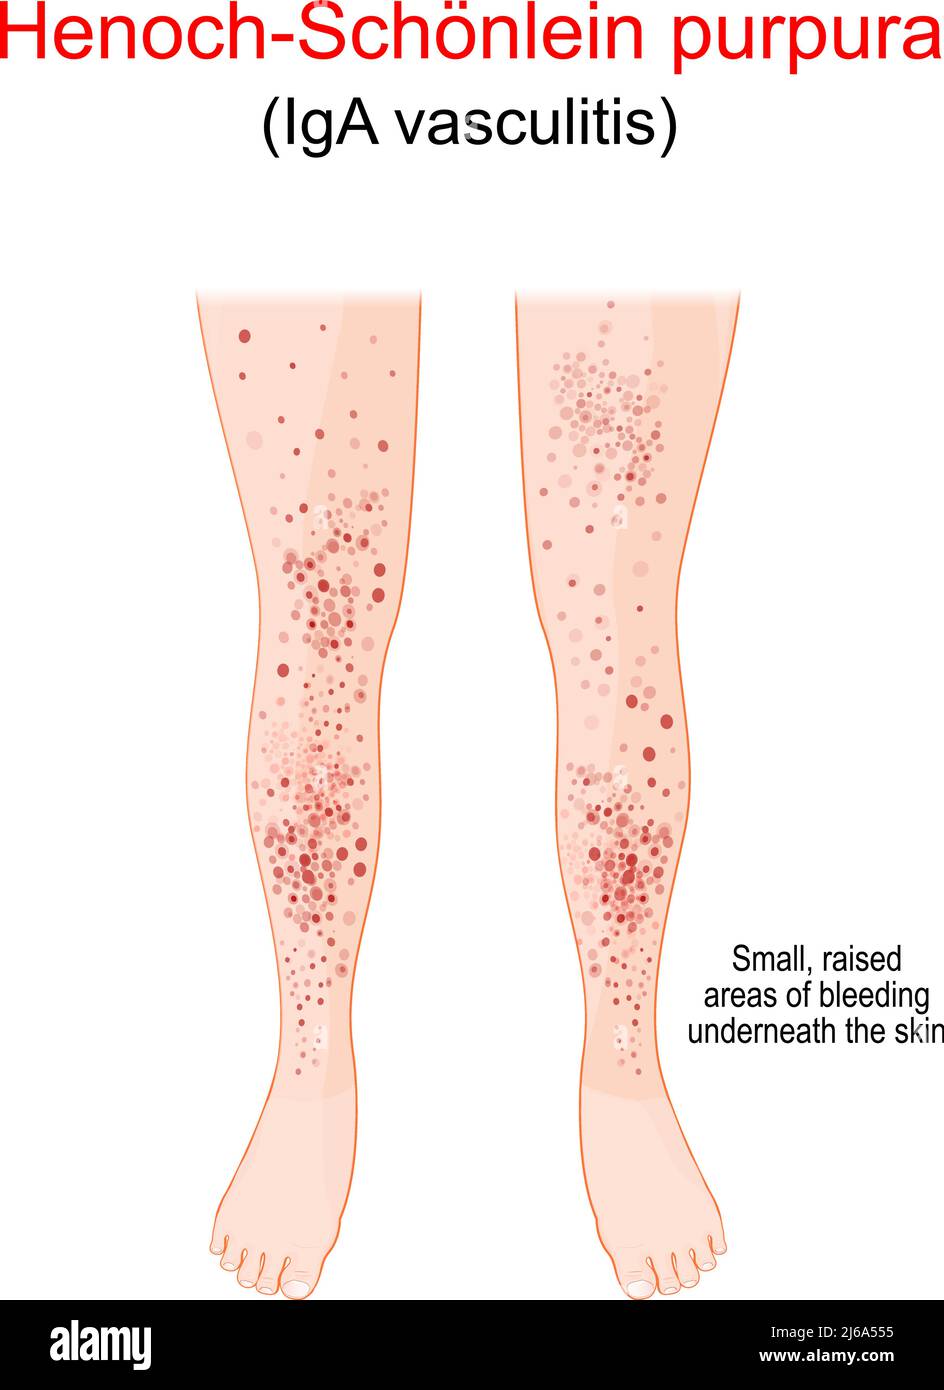

Henoch-Schönlein purpura. Spotty rash on the humans legs. The spots are caused by bleeding underneath the skin, vascular or coagulation disorders Stock Vectorhttps://www.alamy.com/image-license-details/?v=1https://www.alamy.com/henoch-schnlein-purpura-spotty-rash-on-the-humans-legs-the-spots-are-caused-by-bleeding-underneath-the-skin-vascular-or-coagulation-disorders-image468591457.html

Henoch-Schönlein purpura. Spotty rash on the humans legs. The spots are caused by bleeding underneath the skin, vascular or coagulation disorders Stock Vectorhttps://www.alamy.com/image-license-details/?v=1https://www.alamy.com/henoch-schnlein-purpura-spotty-rash-on-the-humans-legs-the-spots-are-caused-by-bleeding-underneath-the-skin-vascular-or-coagulation-disorders-image468591457.htmlRF2J6A555–Henoch-Schönlein purpura. Spotty rash on the humans legs. The spots are caused by bleeding underneath the skin, vascular or coagulation disorders